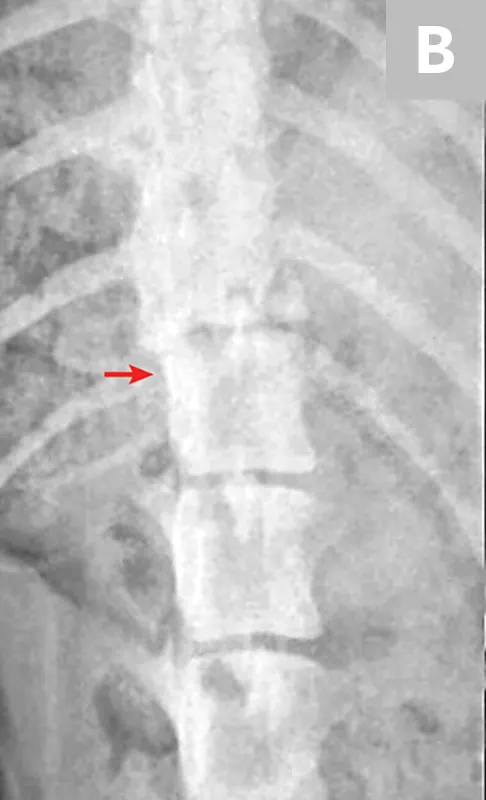

Survey radiographs of the vertebral column should be obtained, as well as chest and abdominal radiographs to assess for concurrent injuries. Horizontal beam radiographs are strongly preferred for obtaining ventrodorsal views of the vertebral column, as they do not require the patient to be moved out of lateral recumbency, which could further compromise the integrity of the vertebral column. Although sufficient for diagnosing significantly displaced vertebral fractures and luxations, radiographs are not adequate for predicting the degree of spinal cord injury or assessing the degree of vertebral instability (Figure 1 and Figure 2).

Figure 1

Lateral radiograph of a dog following unknown trauma. There is a complete oblique fracture (arrow) of the L6 vertebral body and luxation of the L6-L7 articular processes, with severe cranioventral displacement of the caudal segment. Despite the degree of displacement, this patient retained voluntary movement in both pelvic limbs on initial examination and made a functional recovery following reduction and stabilization of the fracture/luxation and 8 weeks of crate confinement.